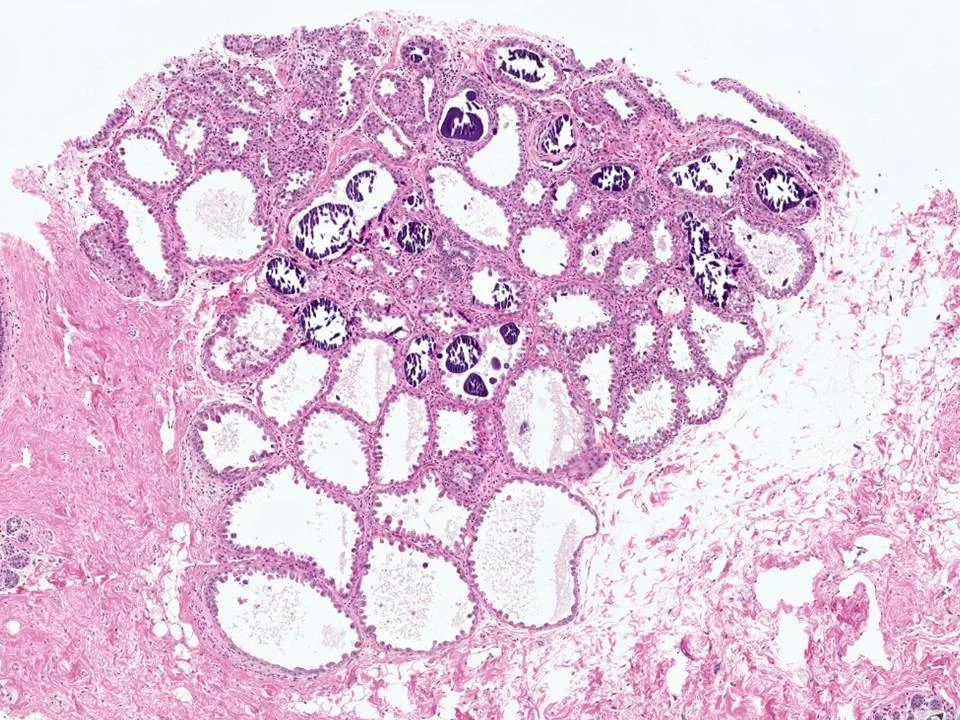

Juvenile Papillomatosis

Presents as a well-defined firm mass that may be mistaken for a fibroadenoma clinically. Grossly, will appear as cysts of varying size. Miscroscopically, cysts and ectatic ducts are seen. Imparts a “Swiss cheese”-like appearance.